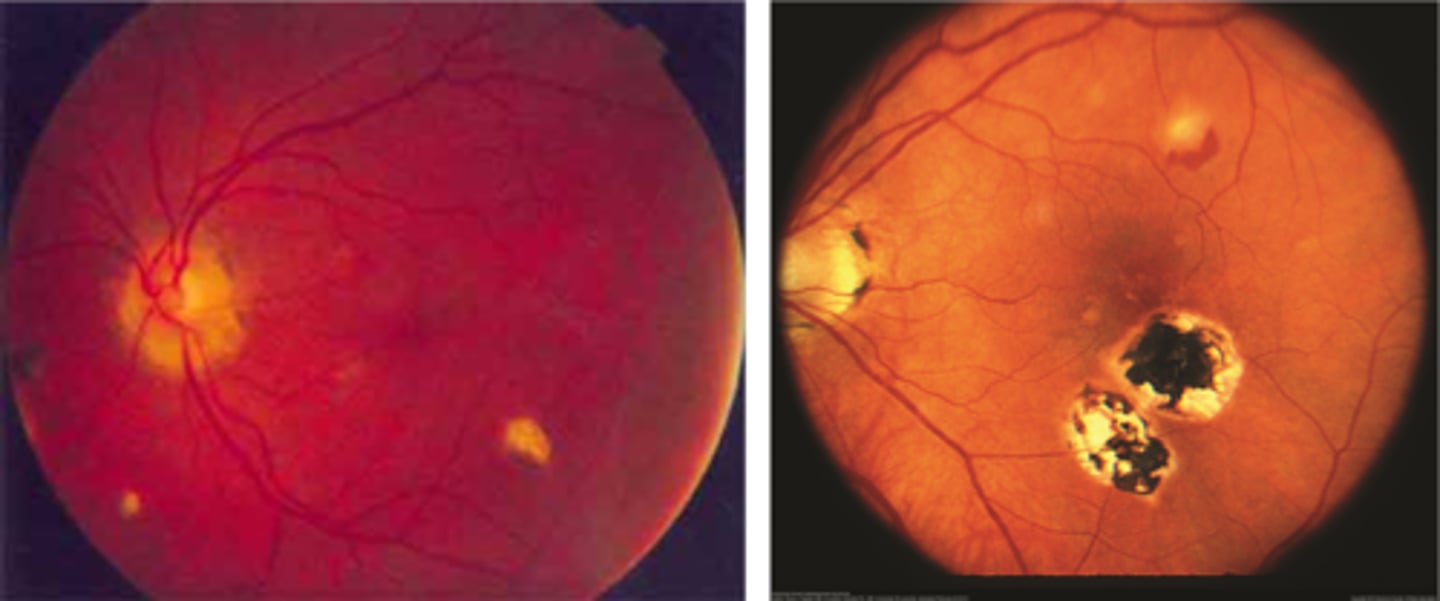

What findings of degenerative myopia are seen here?

PPA

crescent

lacquer cracks

What are lacquer cracks and what causes them?

breaks in Bruch's membrane that can expand and contract, mostly seen in degenerative myopia

How do lacquer cracks appear on fundoscopy?

jagged, irregular yellow lines showing sclera in the posterior pole

What is the main complication of lacquer cracks?

CNV in 29% of pt's